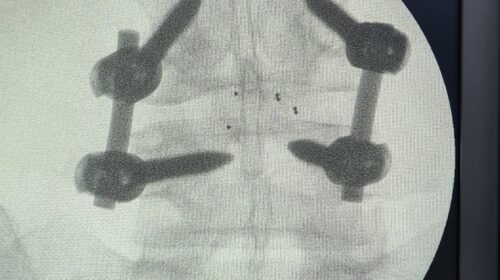

“Fueron tres tipos de exposiciones. Una de ellas es la cirugía en vivo, donde realizamos dos procedimientos en pabellón, acompañados por destacados especialistas, el Dr. Carlos Zanardi, presidente de la Sociedad de Neurocirugía de Buenos Aires, Argentina y el Dr. Cristiano Meneses, director del Instituto de Columna de Brasil”, precisó el Dr. Muñoz.

A continuación, compartimos las fotografías enviadas por el Dr. Avaria a la Sociedad de Neurocirugía de Chile: